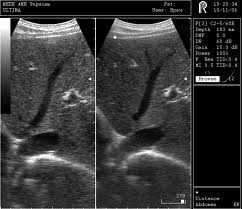

УЗИ печени Печень увеличена в размере, фиброз проявляется в виде снижения эхогенности, а воспалительные участки, где ещё не образовался фиброз, проявляется в виде увеличения эхогенности, контур печени не ровный, волнистая поверхность, стенки воротной вены утолщены, желчный пузырь деформированный и увеличенный, увеличенный диаметр нижней полой вены.